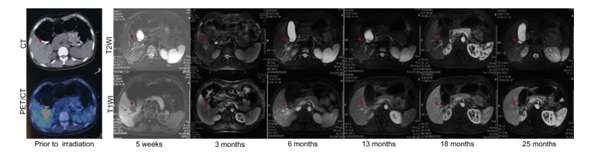

对于肝脏原发或转移瘤肿瘤,射波刀同样因为有同步呼吸追踪的优势,尽管肝脏随着呼吸大幅度运动,但射波刀都可以通过呼吸追踪,精确跟踪肝脏肿瘤的运动,对肿瘤实行多角度无死角杀伤,迄今射波刀因为其卓越的肝部肿瘤疗效,已经成为不适合手术的原发早期肝癌,肝癌术后复发,肝移植术后复发和转移,其他癌种肝转移瘤的主要治疗手段之一。同时,对于早期肝癌射波刀治疗的多项临床实验也在进行之中,初步结果显示了良好的局控和生存。

图9肝癌射波刀治疗疗效(引用自cureus)

图10 肝转移瘤射波刀治疗疗效(病灶治疗后完全消失并且长期稳定,引自Yuan ZY,et al.)